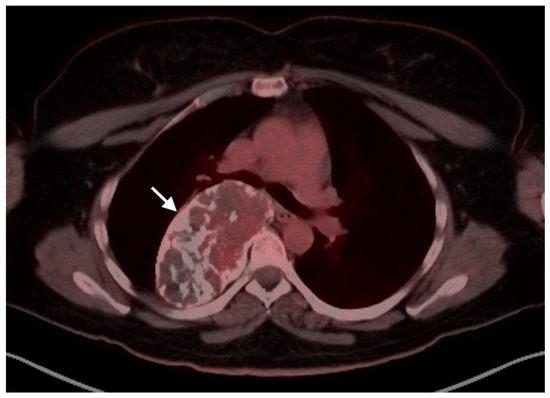

- Camoni, L.; Albano, D. Contrast-enhanced 18F-FDG PET/CT to differentiate primary cardiac lymphoma from primary cardiac angiosarcoma. J. Nucl. Cardiol. 2021, 1–3. [Google Scholar] [CrossRef]